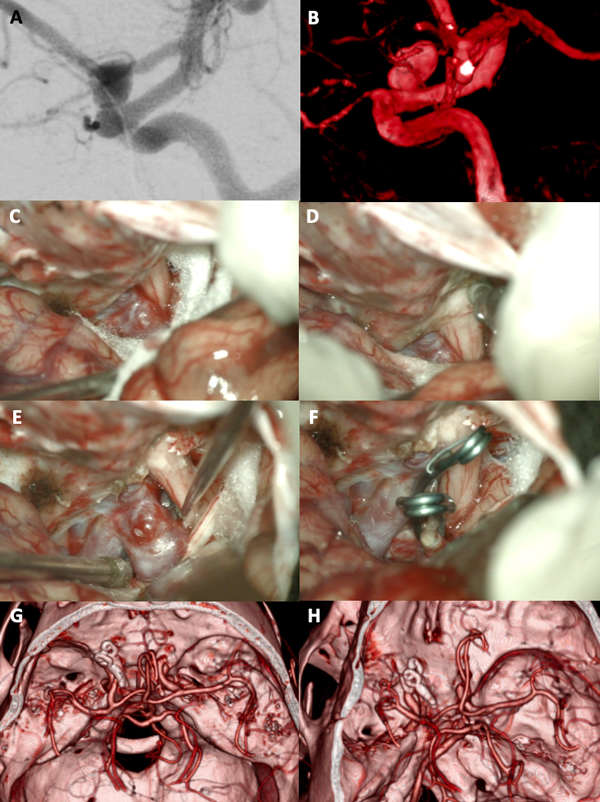

Figura 3. A-B: Se aprecia una arteriografía cerebral con reconstrucción tridimensional que evidencia un aneurisma carótido oftálmico izquierdo. C-F: Fotografías intraoperatorias; observamos la apertura de la fisura silviana con la presencia de la cisterna óptico-carotidea en la profundidad: es visible el saco aneurismático. Posteriormente se realizó un fresado del techo del canal óptico, con lo cual se logró una adecuada exposición del cuello del aneurisma. Se muestra la exclusión del aneurisma con dos clips semi curvos. G-H: Imágenes de angio tomografía post operatoria que evidencia la exclusión completa del aneurisma.